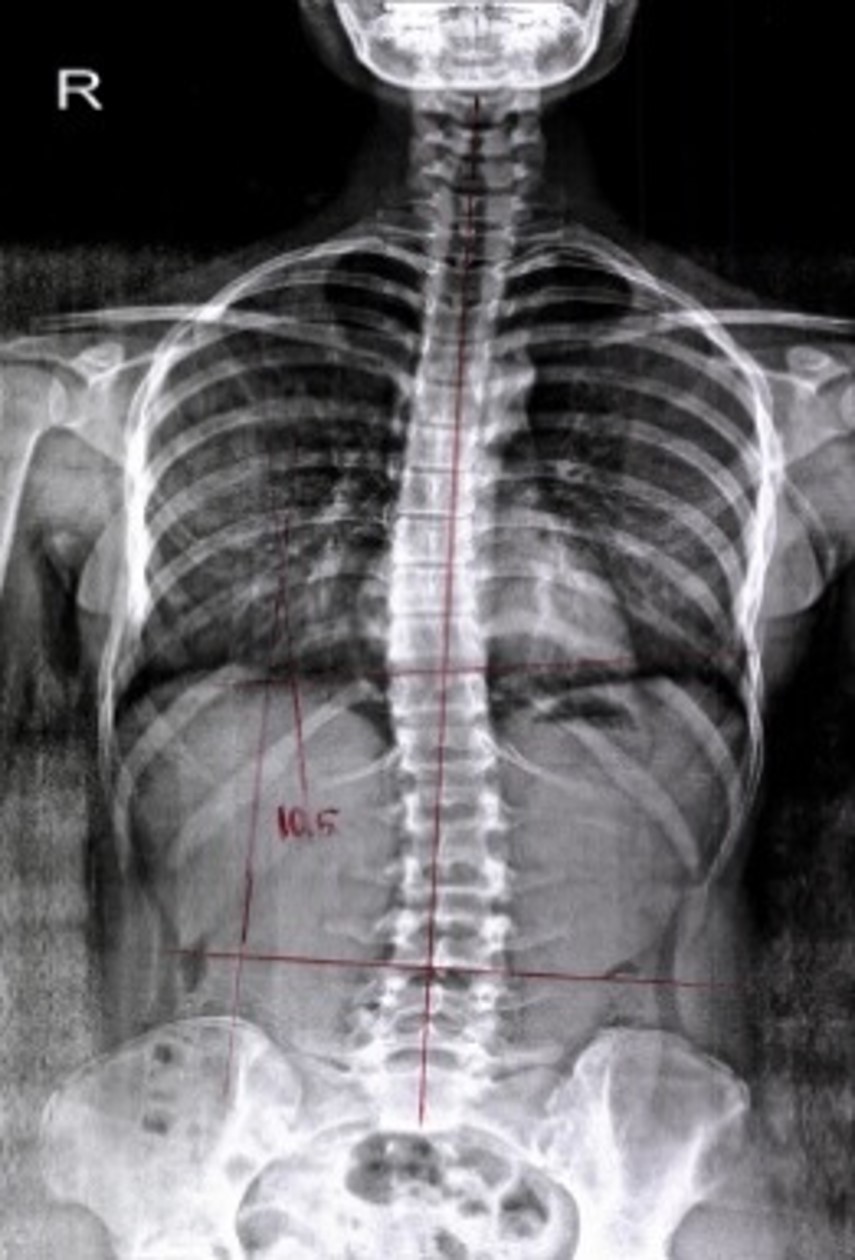

치료 전후 비교

BEFORE

치료 전 척추 엑스레이

치료 전

평균 9.7° 개선

서울 대형병원 임상시험

2024-2025

• 대상자: 특발성 척추측만증 환자 24명

• 치료기간: 주 3회, 12주간 총 36회

• 결과: 100% 환자 Cobb's angle 개선